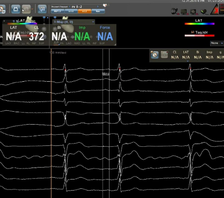

近日,四川省人民医院心脏超声与计算心脏病学团队、结构性心脏病团队于《Quantitative Imaging in Medicine and Surgery》分享的病例,通过多模态超声精准识别舒张期二尖瓣与三尖瓣反流,并成功通过希氏束起搏实现血流动力学逆转,为临床提供了宝贵的诊断与治疗思路。